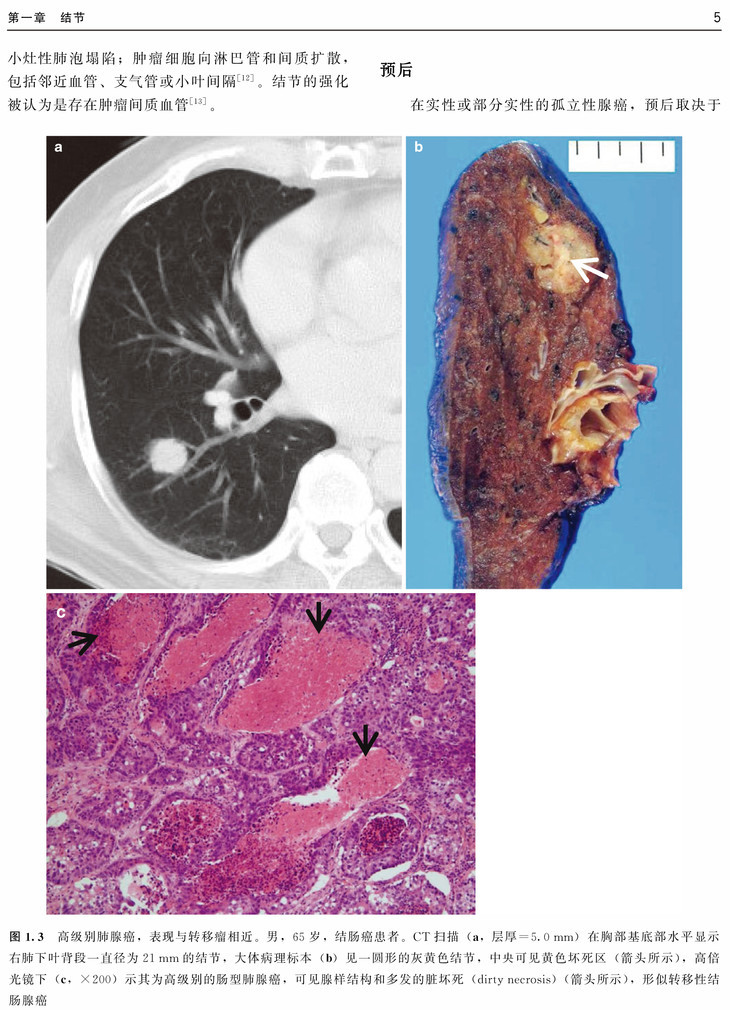

本书以常见肺部病变的CT征象为切入点,从病例入手,涵盖了肺部常见病的组织病理学、临床表现、CT表现、CT-病理对照及预后,并对每类CT征象进行了鉴别诊断总结。